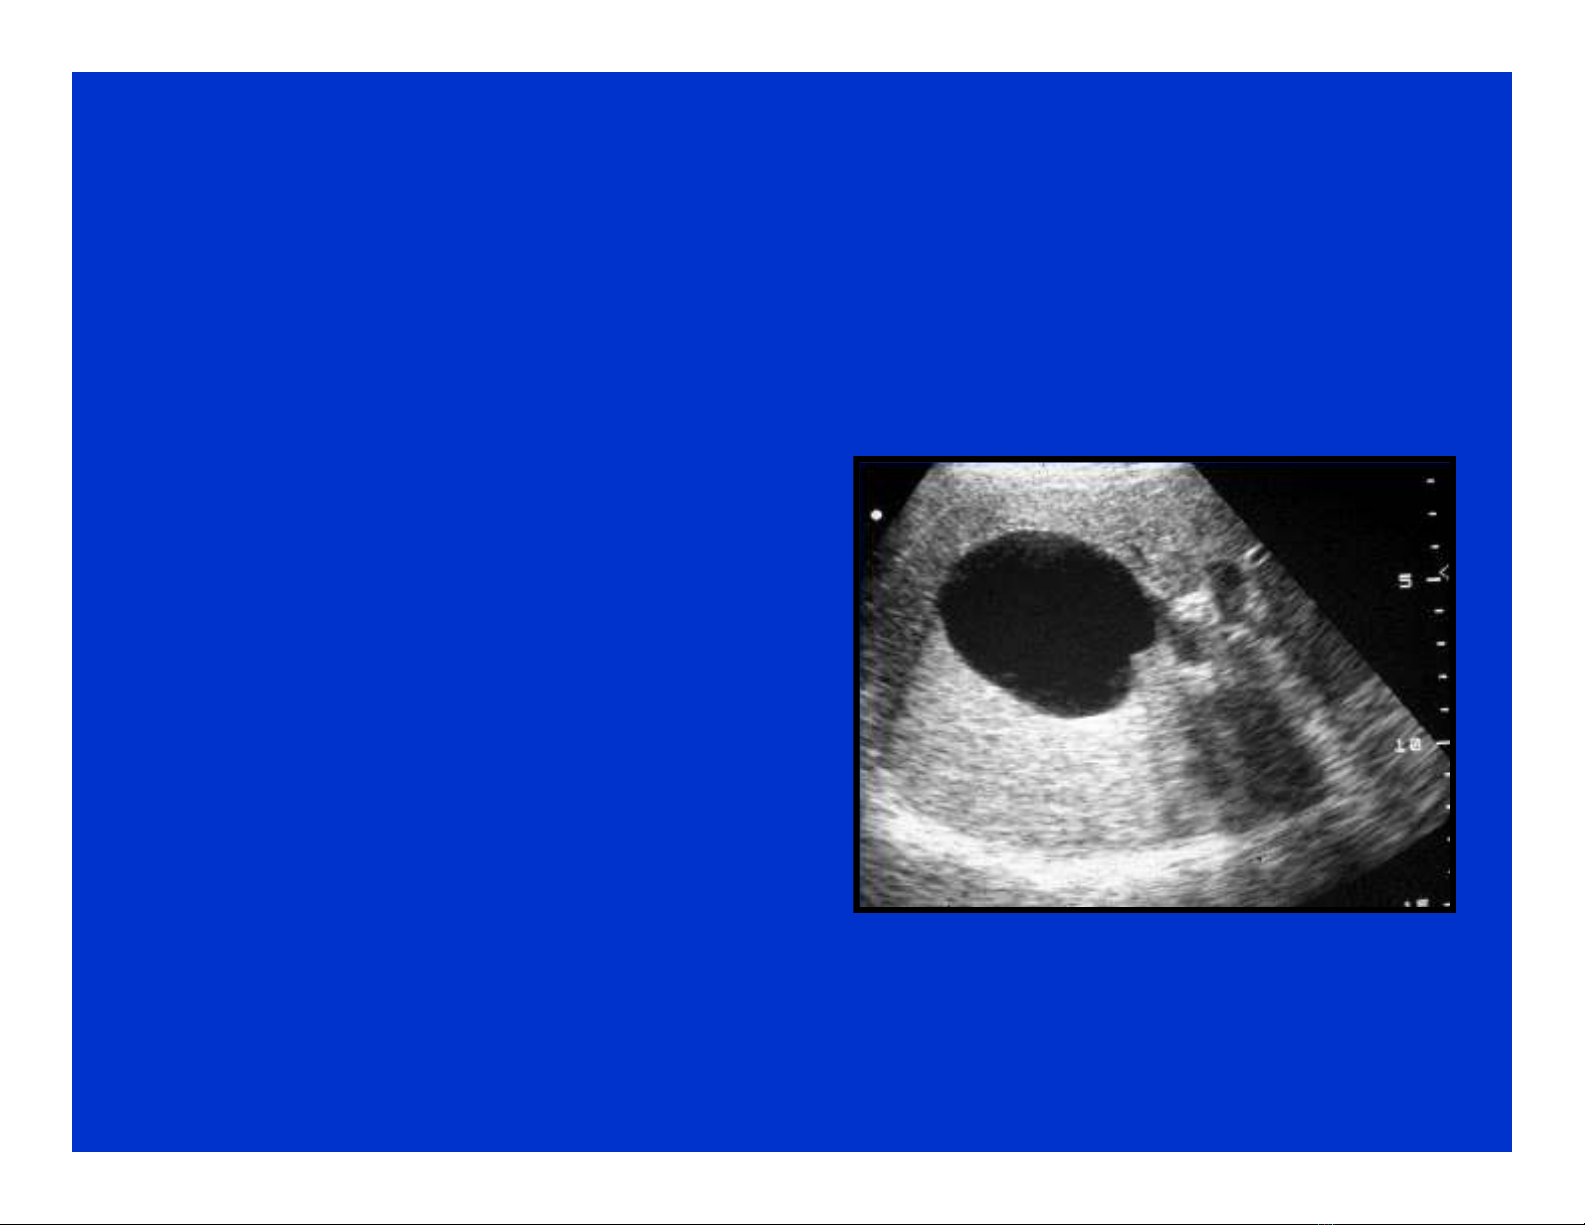

* Rỗng âm (không âm): một

vùng đen, giới hạn rõ và tăng

âm phía sau.

- Rỗng âm hoàn toàn: nang gan.

- Rỗng âm không hoàn toàn:

nang gan có biến chứng (nhiễm

trùng, chảy máu..), áp xe gan,

khối máu tụ, u gan hoại tử, một

số tổn thương u dạng nang…